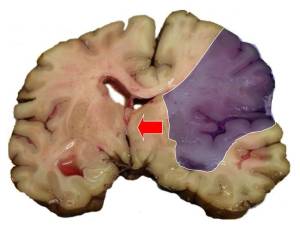

Sağlamlıq Sağlamlıq İnsult – beyin qan dövranının kəskin pozulması nəticəsində baş beyində ocaqlı zədələnmənin yaranması ilə xarakterizə olunur. İşemik və ya hemorragik x Laura's 232 28.10.2024